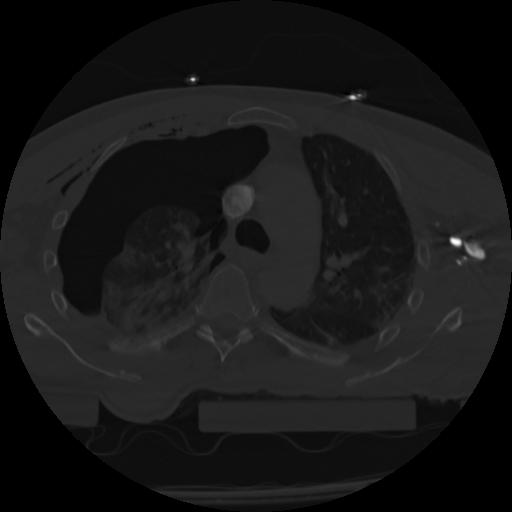

22 ANGIO,CE,Vol,0.5,ANGIO,,